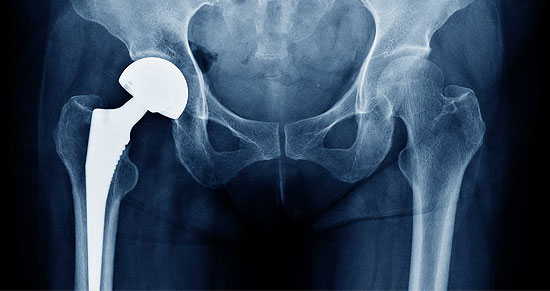

Hip Replacement

Arthritis is the leading cause of disability in India, and the most frequent cause of discomfort